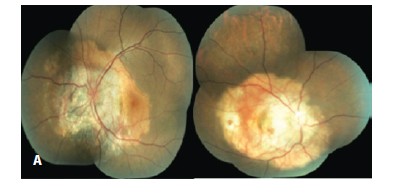

A 28-year-old woman presented with visual loss in the right eye (RE), which was ongoing for 10 days. Her visual acuities were 20/400 in RE and 20/25 in the left. Intraocular pressures were 12 mmHg and 14 mmHg respectively. Anterior segment findings were unremarkable. Fundus examination revealed an orange central fovea (calcified area) surrounded temporally and nasally by a yellow-white region (decalcified area). Her LE fundoscopic exam showed the atrophic choriocapillaris nasal to the disc, a decalcified area between the disc and the fovea, and a calcified area temporally (Figure 1A).

We observed a cage-like reflective pattern with the EDI OCT, which corresponds to the calcified region of the choroidal osteoma (Figure 2A). In some regions, a hyper-reflective band was visible between the calcified tumor tissue and unaffected choroid (Figure 3). The retinal tissue covering the calcified areas seemed intact (Figure 2, 3). FAF imaging of the calcified areas showed slight hyperautofluorescence indicating the integrity of RPE (Figure 1B).

We described three different reflectivity patterns in the decalcified area. First one was a thick hump-like hyper-reflective band, which had posterior acoustic shadowing and had a non-intact RPE overlying it (Choroidal neovascular membrane - CNVM) (Figure 2B). The outer retinal structures (RPE, IS-OS line and external limiting membrane) of the second pattern were disintegrated, the tumor plane was irregular and the vascular structures of the tumor were visible. In addition, the second pattern showed less acoustic shadowing compared to the first one. The third pattern was an irregular hyper-reflective pattern partially beneath or over the RPE and Bruch membrane. In FAF imaging, decalcified areas were mostly hypoautofluorescent although showed hyperautofluorescence in some parts (Figure 1C).

Choroidal thickness was increased in the RE, which had choroidal neovascularization. In addition, intra and subretinal serous fluid was observed. Outer segment elongations similar to the ones in central serous chorioretinopathy (CSCR) were evident. Hyperautofluorescence spots were evident in FAF imaging which correspond to the areas of serous fluid (Figure 1B).